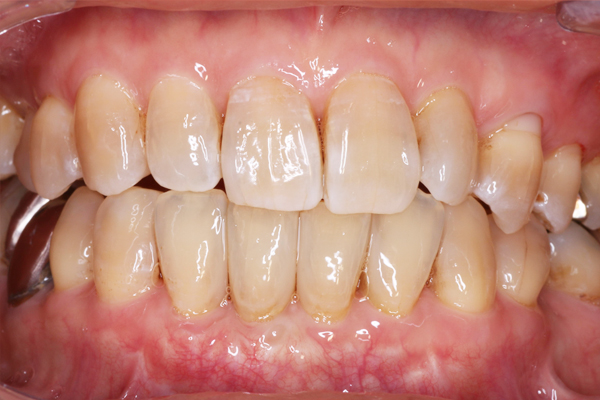

初診時の口腔内写真です。重度の歯周病と多数のむし歯を認めます。

2. 歯周組織再生療法

1. 治療前

右上の前歯に垂直性骨吸収を認めたため、再生療法を行いました。